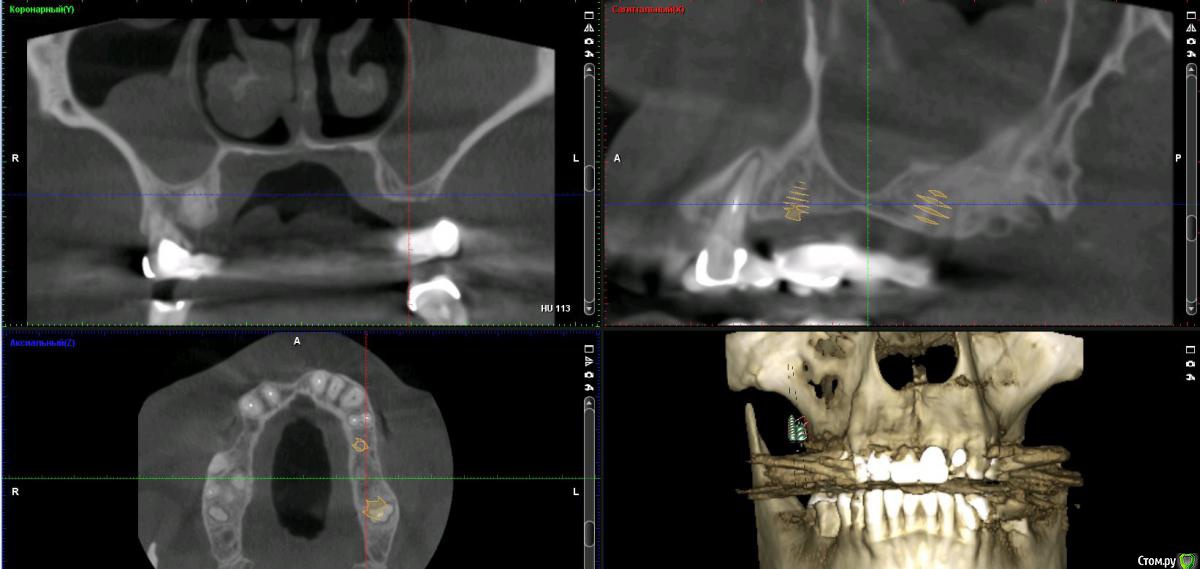

Дмитрий Л. Опубликовано 16 ноября, 2018 Поделиться Опубликовано 16 ноября, 2018 (изменено) Здравствуйте всем)Ситуация такая: старый мост 24-28. 28 симптоматичен, пациент принимает аб и противовосп. Имеется: - 24 перирадикулярные изменения (асимптомно)- 28 перирадикулярные изменения (обострение)- утолщение слизистой гайморовой (асимптомно)- невозможность имплантации в обл 26 (высота кости не позволяет) Пожелания пациента:- удаление 28 - желание сохранить мост - имплантация - нежелание носить съемную конструкцию Как планирую я:- перелечить 24, кальций 2-6 мес.- удалить 28- изготовить съёмник- выждать 4-6 мес. Повторить КТ, оценить гайморовую- имплантация 25, имплантация "где-то в обл 27" - всеми силами избежать синуса Мои грёзы:1. Ставить вблизи 24 - риск. Нужно лечить 24... реэндо... долго... может удалить? 2. Я верю, что причина хр гайморита - 28. Так ли это? Стоит ли ожидать позитивной динамики? 3. На сколько уйдёт кость после удаления 28 за 4-6 мес.? Её и так мало... Станет ли меньше? Графтить 28 не хочу. Там микробы. 4. Объём кости в обл 27-28 требует коротышку. Первыми приходят на ум Штрауман 6 мм (4 мм в кости, станет красиво) или ЭниРидж (бикортакально, скорее всего в пазуху на 1-2 мм). Нюанс в том, что я не работал этими системами... И коротышки не ставил. В общем придётся искать наборы, но это мои проблемы. 5. Итоговая конструкция: мост 25-27. При чём 27 имеет длину 4-6 мм, не слишком ли короткая дистальная опора? Вот спланировал приблизительно так... Надеюсь на отклик. Изменено 16 ноября, 2018 пользователем Дмитрий Л. Ссылка на комментарий

Irouil Опубликовано 16 ноября, 2018 Поделиться Опубликовано 16 ноября, 2018 Если пускаться во все тяжкие, то 2.4-2.5-2.7 одномоментно с нагрузкой в течении недели (или сразу), так вообще надёжнее всего. Но решения о реэндо зубов я не принимаю, так как я их не лечу и не знаю насколько это сложно для конкретного терапевта. Если отсроченно - удалил бы 2.8, принял совместное решение о 2.4, назначил бы туалет носа через 4 недели после удаления на месяц, по окончанию этого срока повторное кт верхней челюсти и пазух с соустьем, принимать решение по новым исходным данным 2 Ссылка на комментарий

колесников Опубликовано 17 ноября, 2018 Поделиться Опубликовано 17 ноября, 2018 Не пойму о чем речь. 24 удаляется. Прекрасно проходят 24,25,27 без синусов (ну может 1 витком у 27го за дно бы зацепился,но это не точно. Когда у пациента случится обострение в пазухе,он пойдёт к ЛОРу ,а тот скажет -всему виной стоматологи,удаляйте Имплант, даже клкт «до» не помогает разъяснить происходящее,пациент остаётся с сомнением,ведь Доктор так сказал! А стоматолог как известно не врач,его слушаем в пол уха. Не советую в такую пазуху заходить.На 27 широкий формирователь,24,25 с нагрузкой. Возможно сст у 24,смотря как удаление пойдёт, 25 раскрыть роллом. Будет и красиво и быстро и функционально 2 Ссылка на комментарий